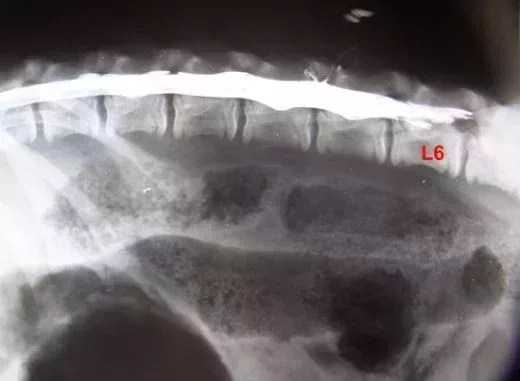

Je jette un oeil à la radio de la myelo passée quelques semaines auparavant pour constater que le cône médullaire n’est pas bas (= après S1) comme le demanderait une FTM élevée, mais qu’au contraire, le liquide de contraste qui s’arrête au cul de sac dure mérien se retrouve vers L5…ou L6 selon les clichés….tous pris au cours de la même anesthésie. De là à dire que le positionnement de l’ensemble varie selon les positions….?

voici ces trois clichés dans l’ordre que je pense chronologique, suivis d’un cliché des premières cervicales qui ne me semblent pas bien alignées effectivement comme on pourrait s’y attendre.

Le sac dure mérien varie d’une vertèbre et demi dans sa terminaison entre le début et la fin de l’anesthésie…comment interpréter cela ?? Une simple migration du liquide de contraste ?